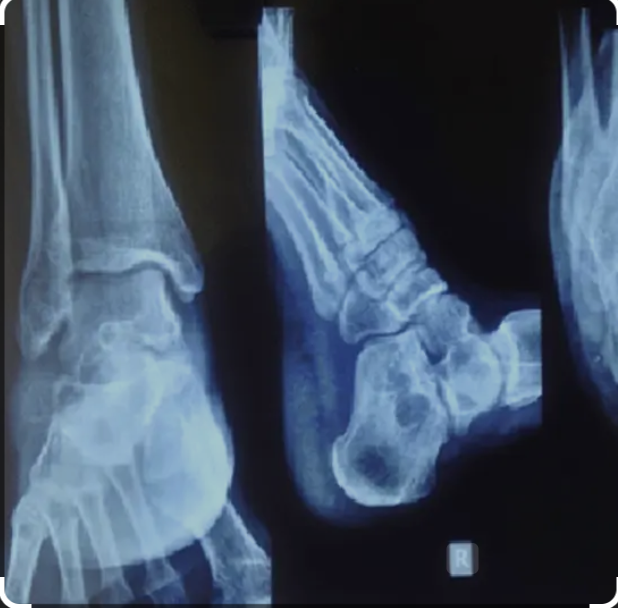

X-ray of Both Heels in Lateral View

Medifyhome provides X-Ray Both Heel Lat View at affordable costs with high-quality facilities. An X-ray of Both Heels Lateral View is a specialized diagnostic imaging procedure that provides a detailed side-view image of both heels, capturing the bones, joints, and surrounding soft tissues with high clarity. This imaging test is commonly recommended for individuals experiencing heel pain, injuries, or suspected bone abnormalities.

The lateral view is particularly useful for evaluating conditions such as fractures, heel spurs, arthritis, plantar fasciitis, Achilles tendon disorders, and bone infections. Since the heel bears the body’s weight and plays a crucial role in movement and posture, any discomfort or structural abnormalities in this area can significantly impact daily activities. One of the key advantages of this test is its non-invasive and painless nature, requiring only a small dose of radiation to produce high-resolution images for accurate diagnosis. We collaborate with NABL and NABH-certified diagnostic imaging centers to offer cost-effective yet high-quality X-ray tests. Book an x-ray with Medifyhome today by checking our website or calling +919100907036 / +919100907622 for the most affordable and hassle-free medical treatment.

An X-Ray Both Heel Lateral (Lat) View is a diagnostic imaging procedure that captures side-view images of both heels. It focuses on the calcaneus (heel bone) and surrounding structures, such as joints and soft tissues. This view provides a clear perspective of the heel’s alignment, shape, and any abnormalities. It is commonly used to evaluate conditions like fractures, heel pain, arthritis, infections, bone spurs, or tumors. The procedure is quick, non-invasive, and involves minimal radiation exposure, making it a valuable tool for diagnosing and managing heel-related issues.